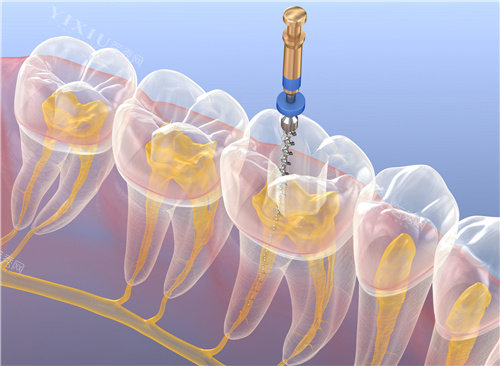

机构内配置的影像设备可拍摄多角度口腔图像,辅助医生判断牙齿根管形态及骨组织情况。扫描设备能够获取牙齿三维数据,用于制作修复体模型。部分仪器具备实时监测功能,在治疗中辅助调整操作细节。

该机构在复杂牙病处理上形成特色,如针对牙周病患者的种植前处理,通过系统治疗控制炎症后再进行手术。对于多颗牙缺失病例,采用分段种植方案降低手术创伤。在美学修复领域,重视前牙形态与面部比例协调性,通过比色板选择接近天然牙的修复体颜色。